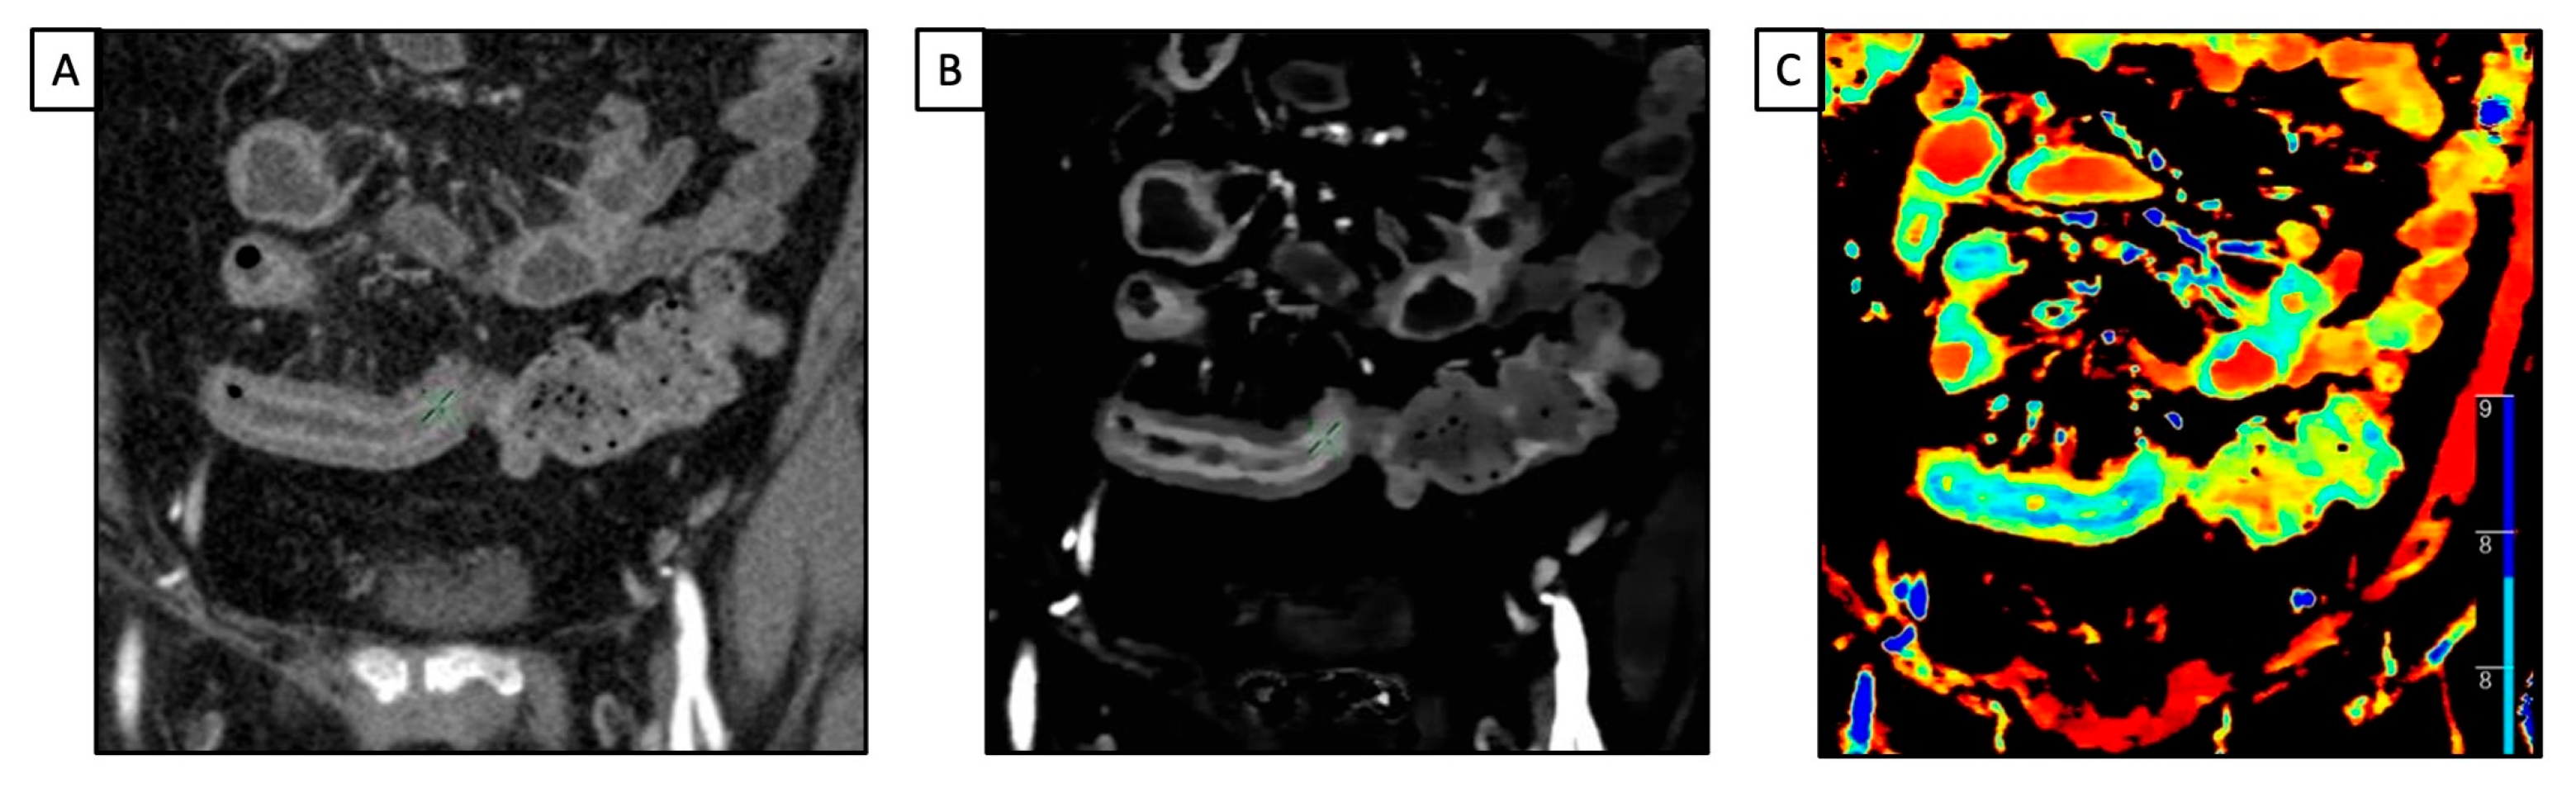

- Taguchi, N.; Oda, S.; Kobayashi, T.; Naoe, H.; Sasaki, Y.; Imuta, M.; Nakaura, T.; Yamashita, Y. Advanced Parametric Imaging for Evaluation of Crohn’s Disease Using Dual-Energy Computed Tomography Enterography. Radiol. Case Rep. 2018, 13, 709–712. [Google Scholar] [CrossRef]